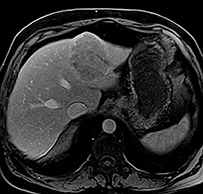

La cicatrice de thermoablation se présente sous forme d’une image nodulaire avasculaire, spontanément hyper intense T1 avant injection, en rapport avec la nécrose de coagulation (figure 2).

Une récidivé loco-régionale se présente sous forme de prise de contraste nodulaire sur les berges de cette cicatrice. Les séquences en pondération T2 ou en diffusion pour diagnostiquer la récidive sont plus difficiles à interpréter car il persiste longtemps après le geste une hyper intensité T2 au sein ou au pourtour de la cicatrice.

| Carcinome hépato-cellulaire de 45 mm de diamètre, typique en IRM chez un patient de 75 ans, porteur d’une cirrhose éthylique et dysmétabolique incomplètement sevrée, Child A avec une alfafoetoprotéine normale. La clairance au vert d’indocyanine très pathologique à 34% à 15 min (Nle <15) a fait contre-indiquer un traitement chirurgical. | |